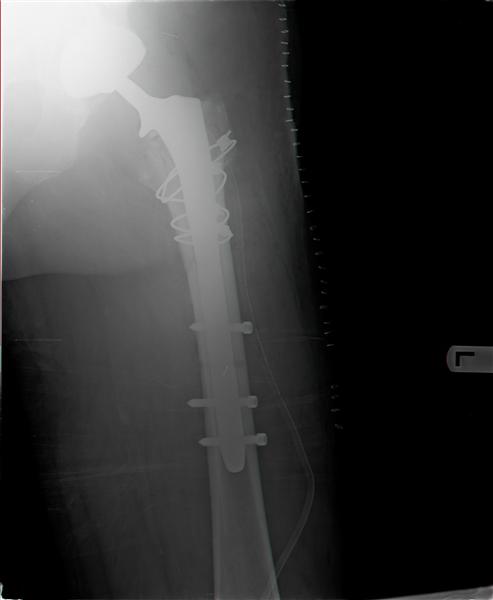

Socket is acceptable position so wasn't change.Fracture proximal femur -

three part I min G.T & L.T. After removal femoral prosthesis was done

reduction of L.T & Calca. Reaming and insert new prosthesis with distal

locking by 3 screws,reduction G.T.and fixation by 4 cyrclages.

Connection head and reduction femur.In the end surgery got stable joint.

Here x-ray after operation.